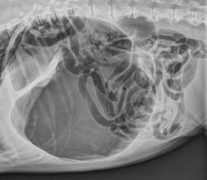

胃の疾患 ~ 胃拡張・胃捻転症候群(胃捻転)

胃拡張・胃捻転症候群(gastric dilatation-torsion(volvulus)syndrome)胃の膨満を特徴とし、処置が遅れると生命にかかわる重大な急性疾患です。胃の単純な拡張を示すものと捻転を伴うものとの2型があり、後者...

胃の疾患 ~ 胃食滞および胃拡張・胃内の異物

胃食滞および胃拡張(gastric impaction and dilatation)過食した時、または胃内容の十二指腸への後送が妨げられると、胃内容は増加停滞して食滞となる。胃内容が急激に増加すれば、胃壁は拡大して急性胃拡張を発症し、また...